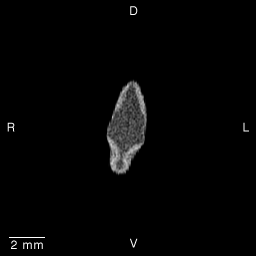

Stage 15 (Day 33), transverse slice 3